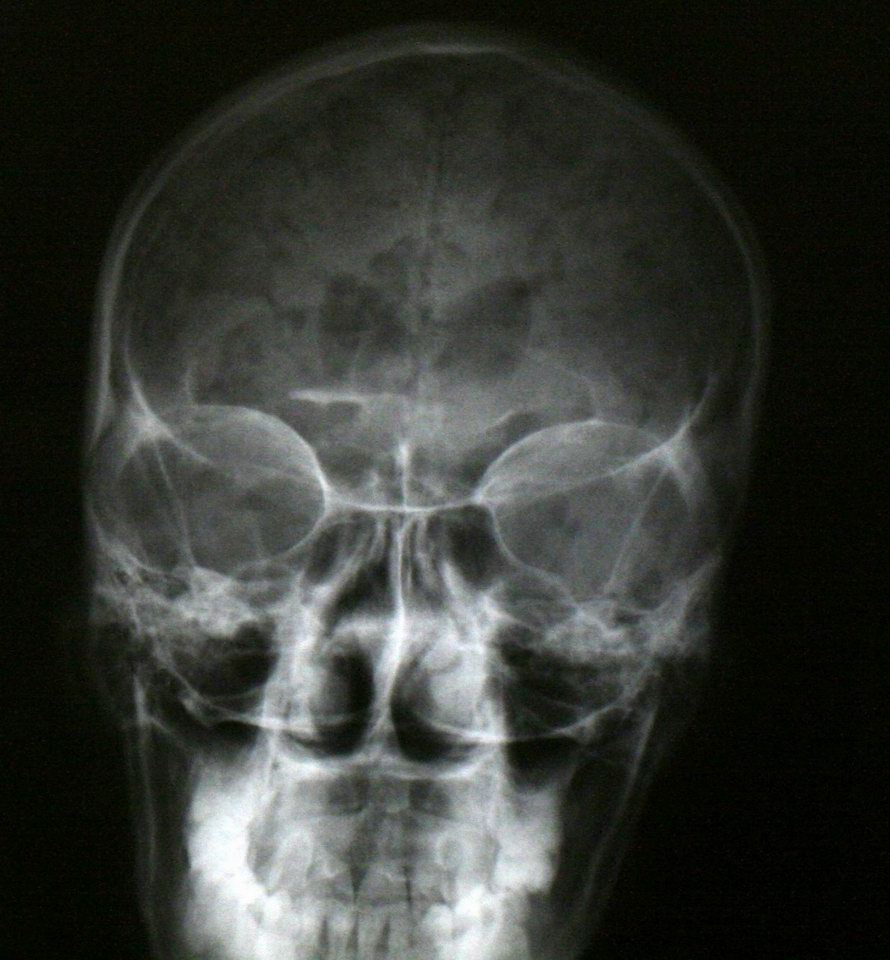

Air in the skull from a stabbing -- "pneumocranium" |

CT of same patient |